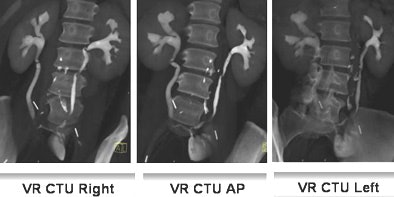

![]() |

| Fifty-three-year-old woman post cystectomy. Three VR CTU images (left to right: right oblique, AP, and left oblique) were created to depict the ileal neobladder reconstruction. Images courtesy of Dr. Terri Vrtiska, Mayo Clinic, Rochester, MN. |